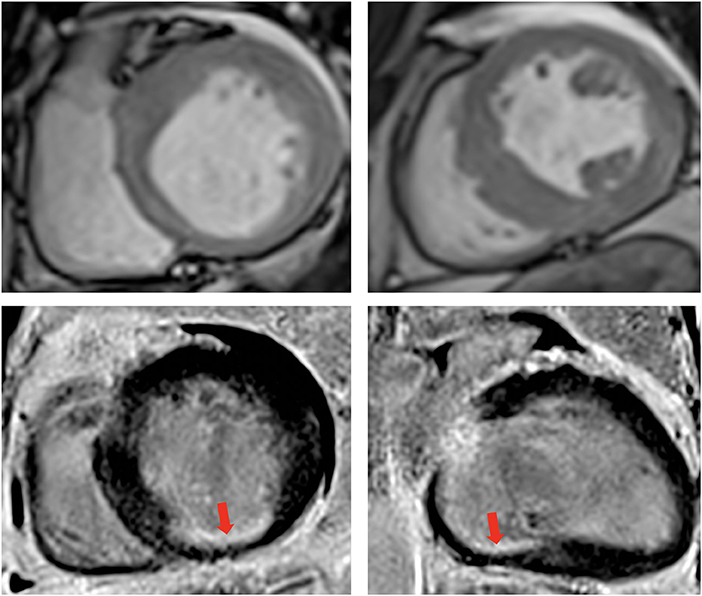

Additionally, cardiac MRI (Figure 2) demonstrated LV dilation (160 ml/sqm) with mild systolic dysfunction (LVEF 41%). T1 mapping values were consistent with diffuse myocardial fibrosis (septal T1 1,100 ms). Late gadolinium enhancement (LGE) protocol revealed subendocardial scar in the basal segments of the inferior wall and the inferior septum/inferolateral wall. Minimal pericardial effusion was seen anterior and lateral to the basal LV.

Figure 2

Contrast enhanced cardiovascular magnetic resonance imaging. Cine images diastolic frames in short axis at the base (top left) and at the level of papillary muscle (top right) showing asymmetrical left ventricular hypertrophy. Late Gadolinium enhancement phase sensitive inversion recovery (PSIR) imaging in short axis (Base left) and 2-chambers view (Base right), respectively, showing the subendocardial scar at the base of the inferior wall (red arrow). The transmurality of the scar was reported at 50–75%, however, note that only one segment is infarcted, while the rest of the territory supplied by the right coronary artery is viable.